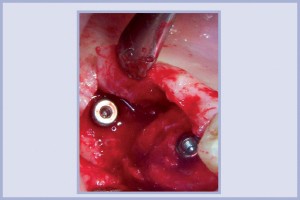

- Fig. 25 – Visione intraorale degli impianti posizionati in zona 1.6 e in zona distale al 1.7